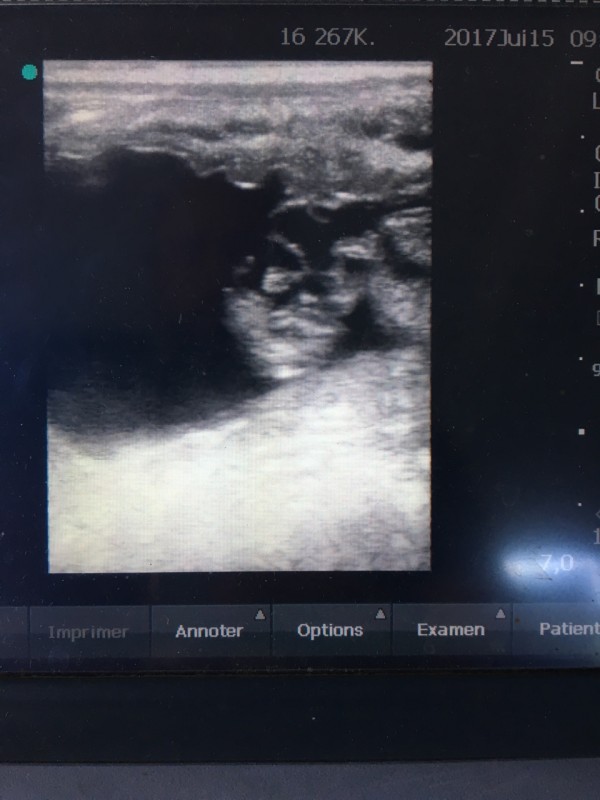

Un petit coeur qui bat !!!!!

Gestation confirmée pour Olympe, écho à 5 semaines, on la laisse tranquille jusqu'à la mise-bas...